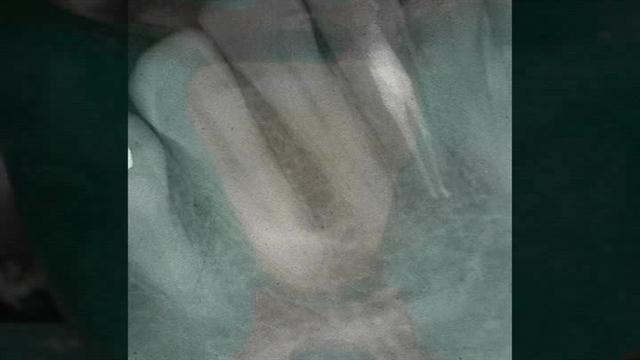

پخش صدا unit 7 dentistry 1 اشتراکگذاری لیست پخش ۰ نظر ۰ نظر گزارش تخلف بیشتر گزینههای بیشتر لیست پخش لایکها گزارش تخلف ۰ لایک nasim منتشر شده در تاریخ ۱۴۰۰/۰۸/۲۲ این کانال دنبال شد دنبال کردهاید دنبال کردن این کانال دنبال کردن ادامه نظرات لبخند لبخند لغو ثبت نظری برای نمایش وجود ندارد.